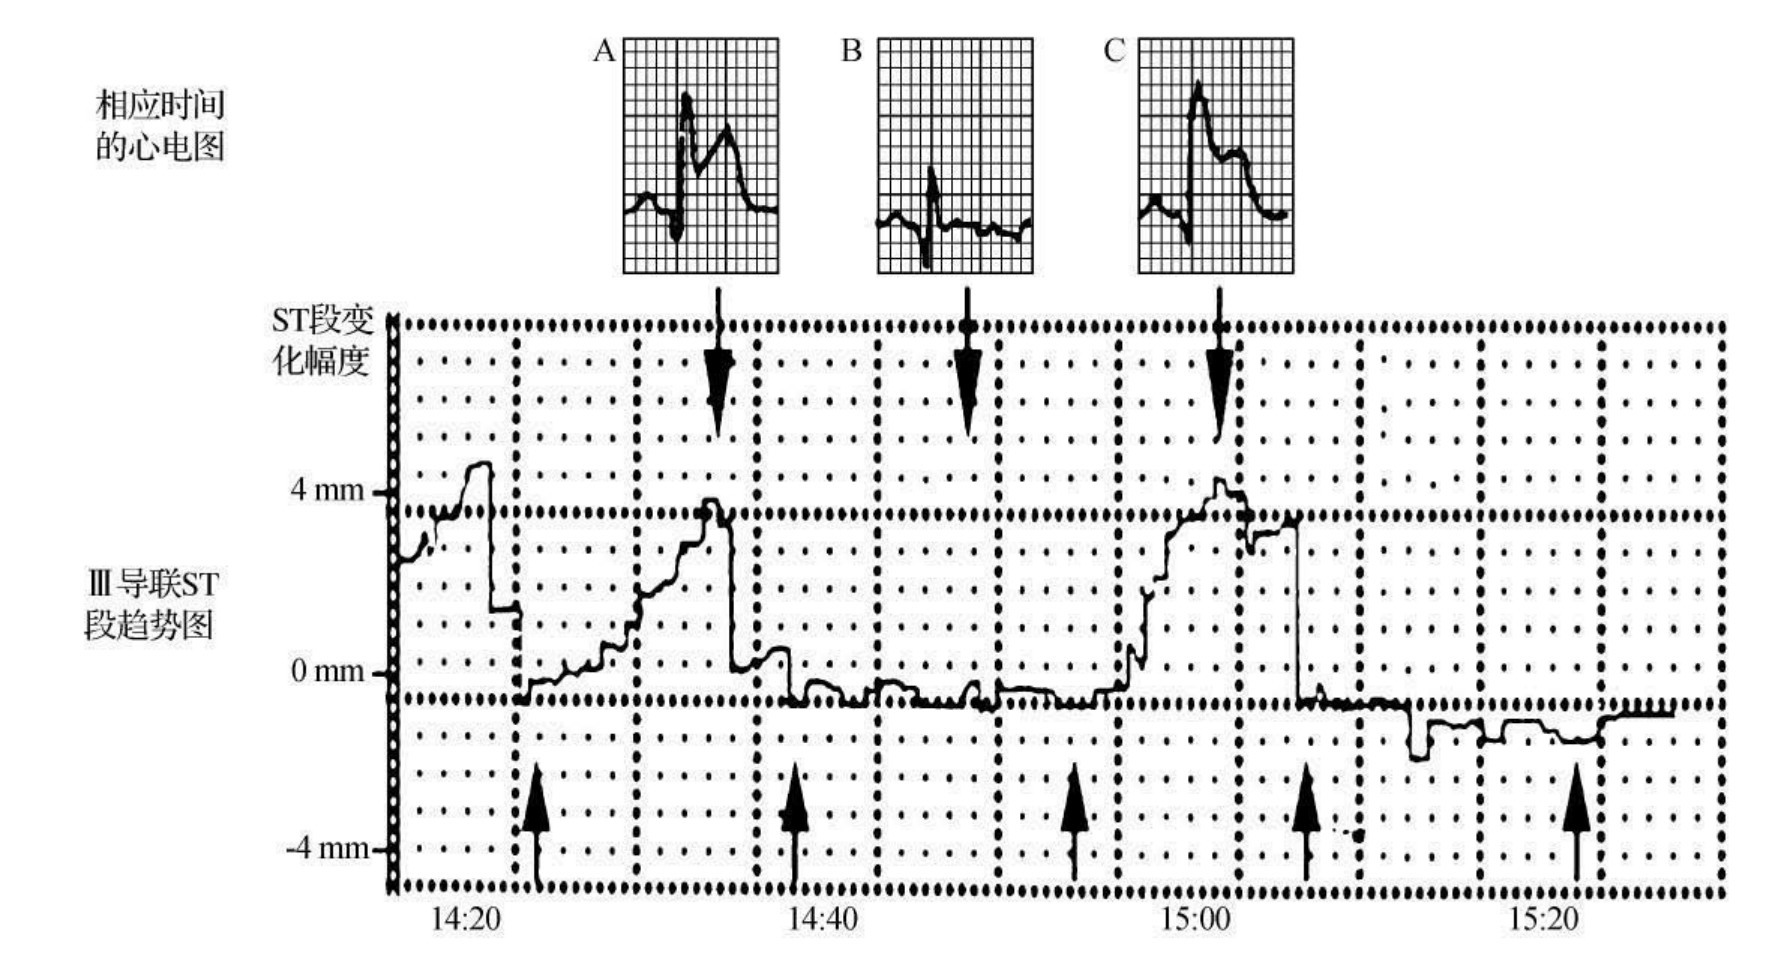

图44-69 心电图缺血指纹

患者女性,76岁。反复胸痛入院。本图是Ⅲ导联ST段改变的趋势图。可以看到动态变化的ST段从正常等电位线(14∶20)到首次ST段明显抬高(14∶35A),随后ST段回到等电位线(14∶40B),以后再次记录到ST段相同的抬高(15∶00,C)。比较不同次心肌缺血A、C心电图后,可诊断发生了心电图缺血指纹的改变

图44-68是一个76岁冠心病心绞痛女性患者的动态心电图剪辑图片,在心电监护过程中发作数次心绞痛。从记录的资料来看,每次心绞痛发作不仅心电图QRS-T波的形态雷同(图A与图C是不同时期心绞痛发作时的QRS-T波形改变,形态雷同),其ST段趋势图也基本一致,符合心肌缺血指纹,诊断为冠心病心绞痛。